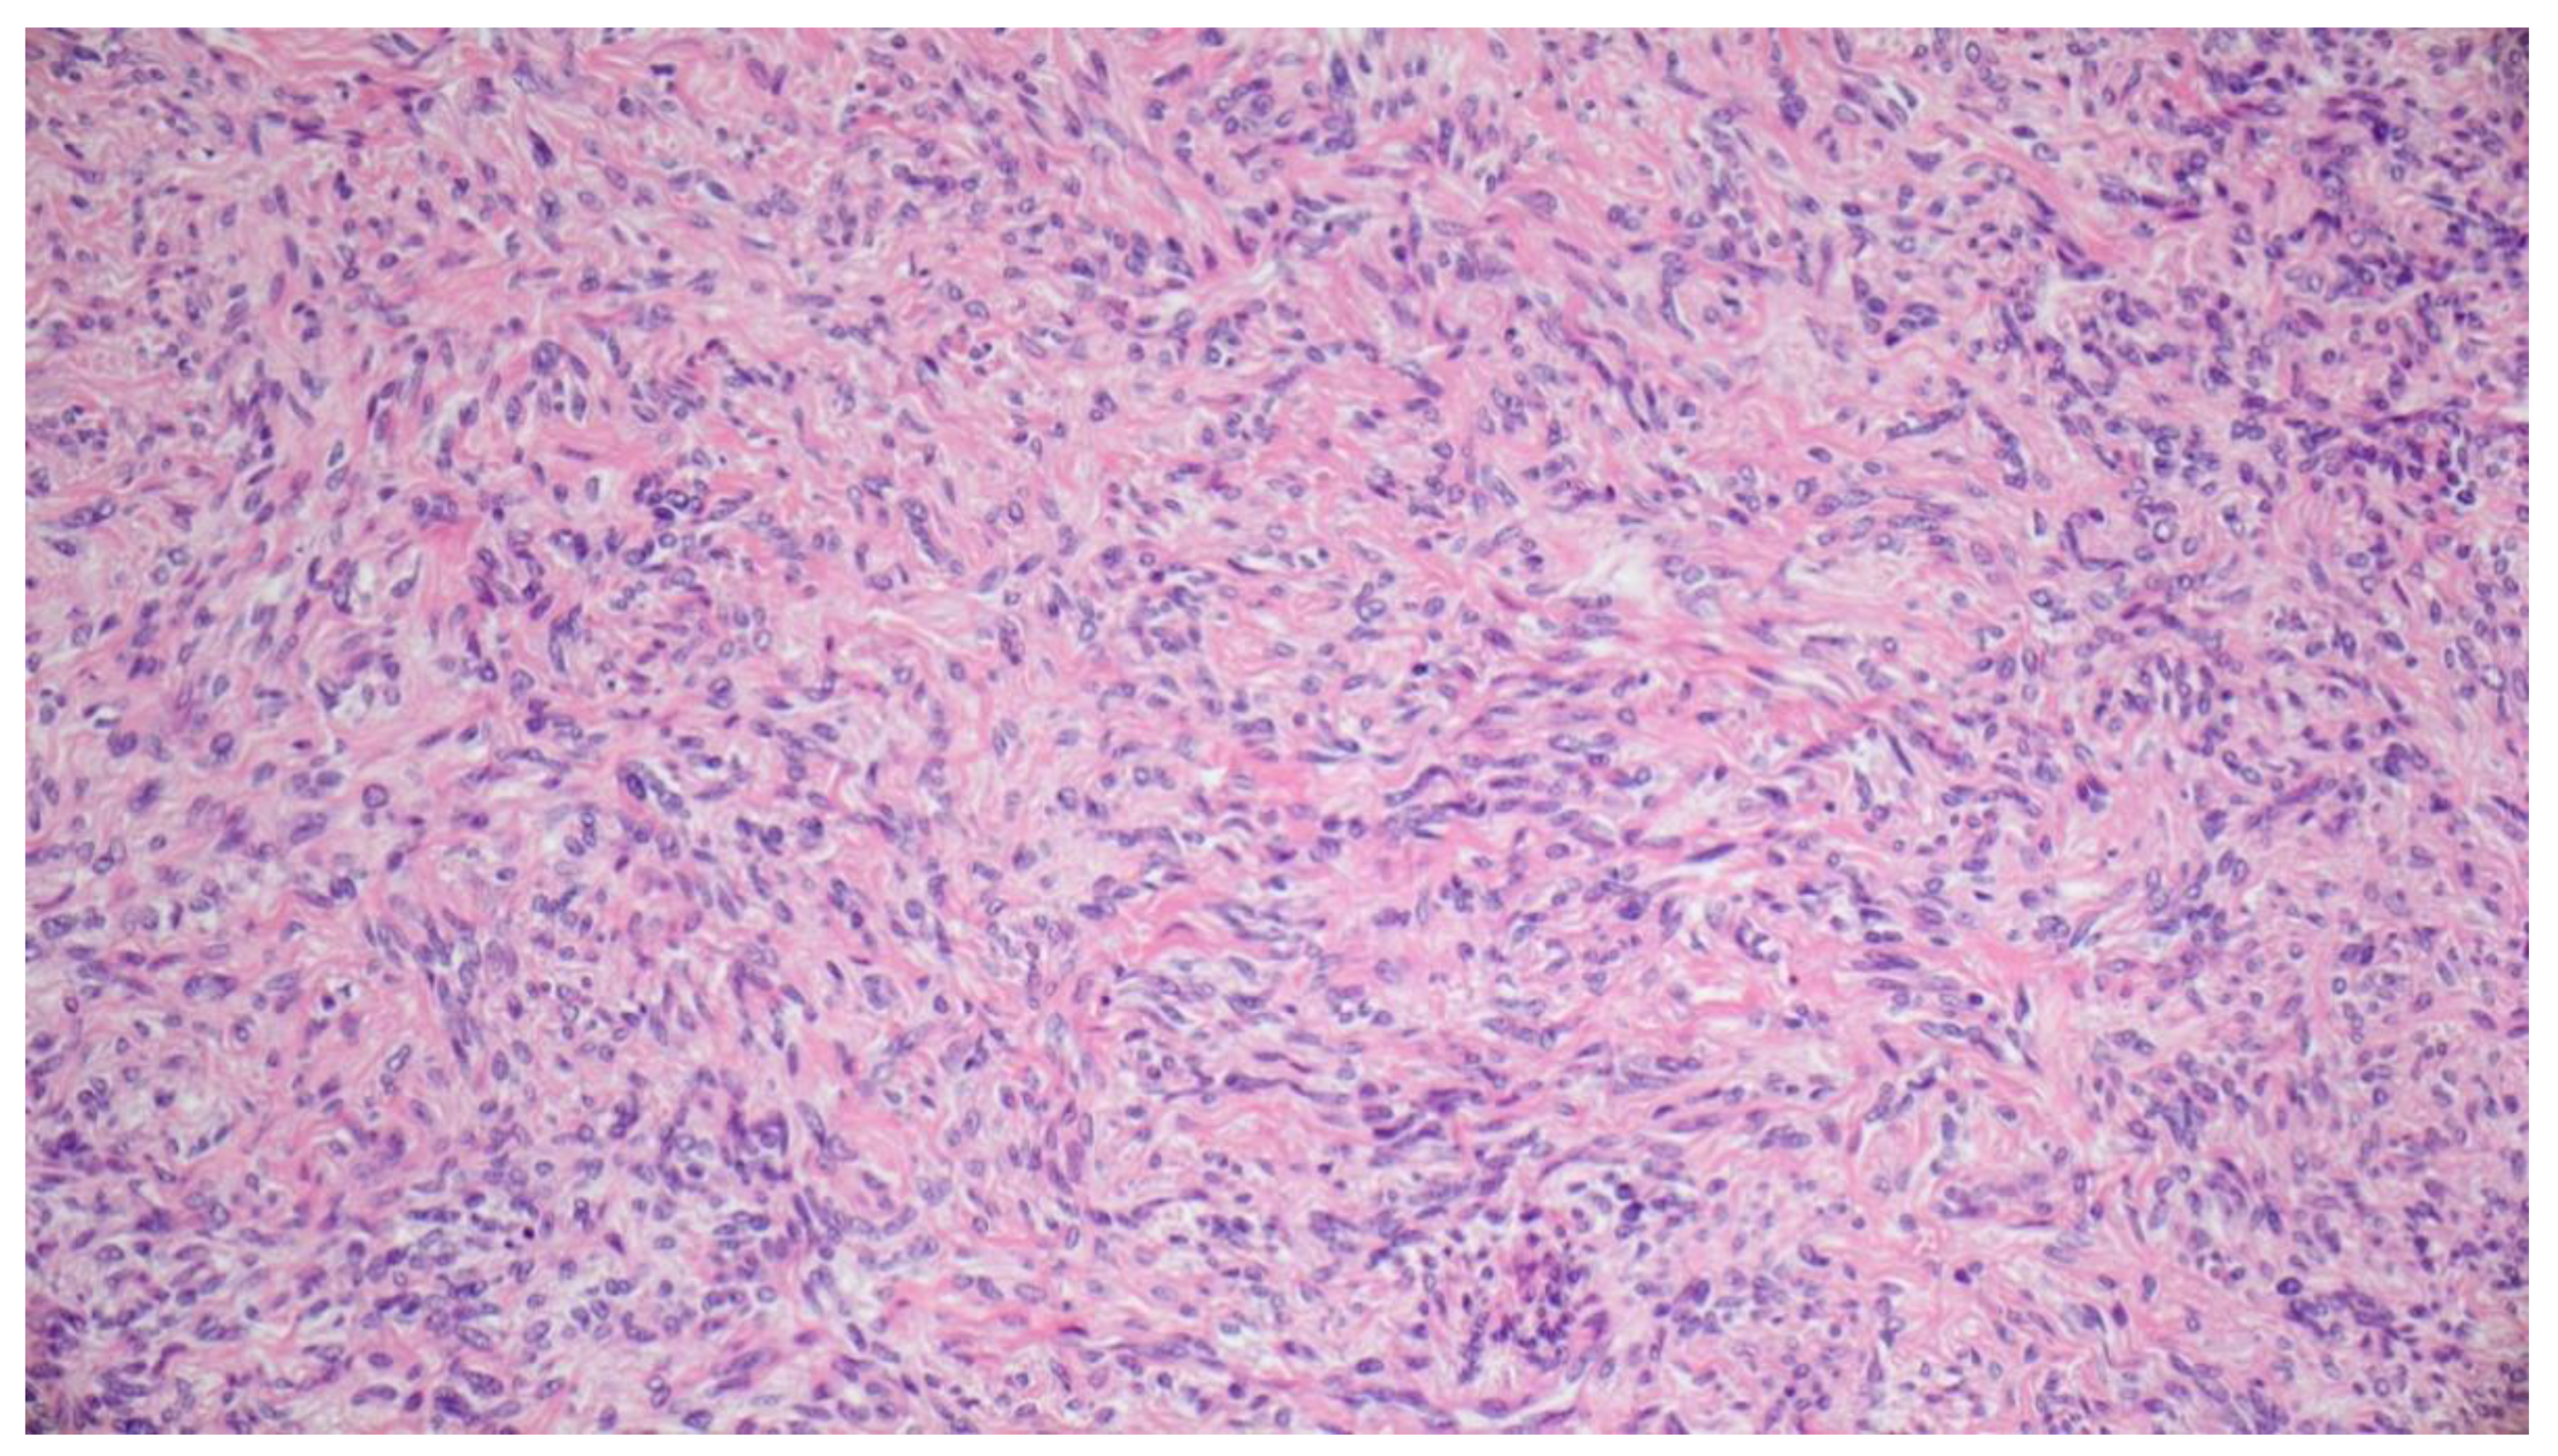

2. Case Report